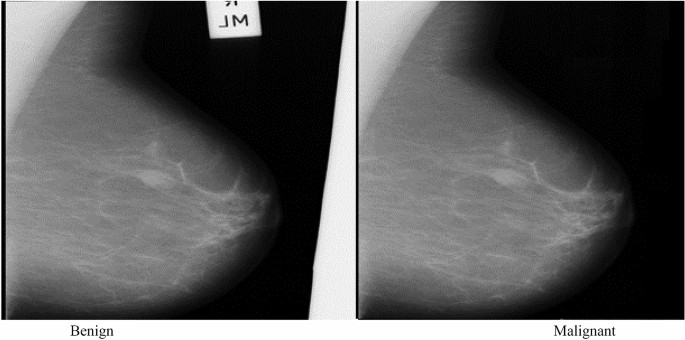

For our data, we will use the breast cancer dataset from scikit-learn. This dataset contains tumor observations and corresponding labels for whether the tumor was malignant or benign.